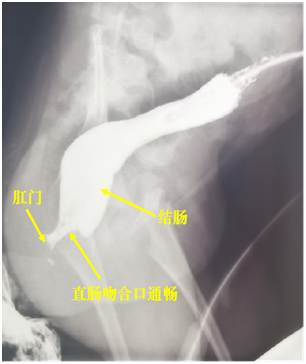

经过3个月的观察,小叶彤生长发育正常,再次进行结直肠造影和消化内镜检查发现直肠与肛门恢复通畅(下图),肛门直肠测压正常。

2021年6月11日,小叶彤再次入院完成最后的关瘘手术,经过新生儿外科医护人员的精心治疗与护理,患儿排便功能正常,可以像其他正常儿童一样通过肛门规律排便,且没有任何并发症出现。现在,小叶彤已经出院,完全回归正常生活。